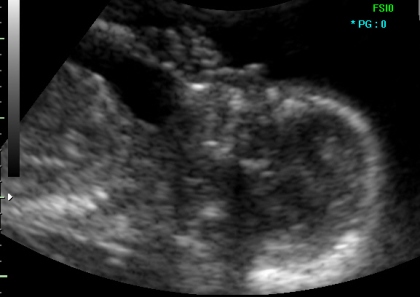

Мајката сеуште не ги чувствува движењата на бебето, но при поставување на сондата веднаш се забележува дека бебето интензивно мрда. Преку прегледите на УЗ мајката постепено станува свесна за постоењето на своето бебе, и веќе значајно се приврзува за него. Исто така, во овој период најчесто се поставува и прашањето за полот. Бебето е сеуште многу мало, па прогнозата на полот не е сигурна.

Во продолжение Ви презентираме неколку УЗ слики од прегледот во 12. недела.